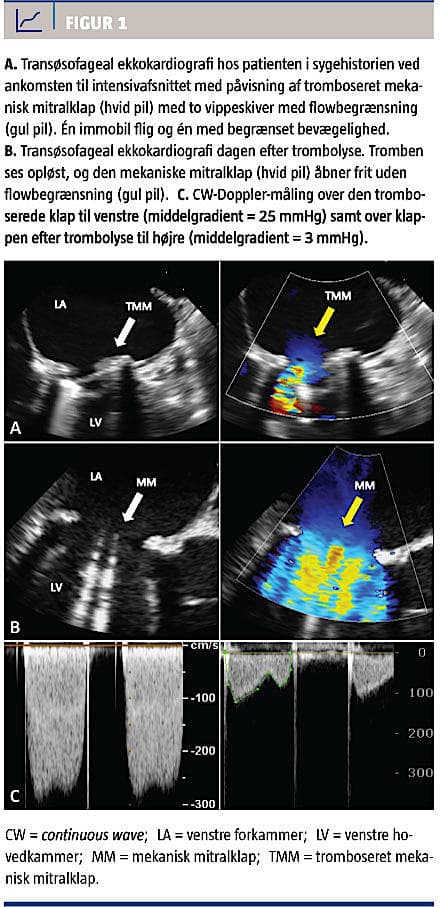

Sygdomsforløbet, som førte til indlæggelsen, debuterede med åndenød, tør hoste og rallende vejrtrækning, der forværredes i liggende stilling, samt respirationssynkrone retrosternale smerter. Der var ikke beskrevet mislyde. Patienten henvendte sig på sit lokalsygehus to gange. Her fandtes han afebril med normale infektionstal, dog gav stetoskopi mistanke om pneumoni, og et røntgenbillede af thorax blev tolket som visende et diffust højresidigt underlapsinfiltrat. Patienten blev sendt hjem med penicillin. På fjerdedagen henvendte han sig igen. Han var da akut påvirket, dyspnøisk og klamtsvedende. Blodtrykket blev målt til 101/58 mmHg, pulsen til 102 slag pr. minut, SaO2 var 99% på 10 l O2 og laktatniveauet var 7,8 mmol/l. Røntgenbilledet af thorax viste nu pleuraekssudat, atelektase og lungestase. En transtorakal ekkokardiografi viste en velfungerende venstre ventrikel med en lille kavitet samt høj middelgradient på 26 mmHg over mitralklappen. Der opstod mistanke om akut trombosering af mitralklappen, og der blev givet 10.000 IE heparin i.v., hvorpå patienten blev overflyttet til en intensivafdeling på et hjertecenter. Han var sederet og intuberet, og der blev påbegyndt noradrenalinbehandling pga. et nu lavt blodtryk på 83/49 mmHg og et forhøjet laktatniveau. Der blev foretaget en akut transøsofageal ekkokardiografi, hvorved det blev bekræftet, at der var en tromboseret mitralklap med en immobil vippeskive og en med begrænset bevægelighed (Figur 1). Tromben vurderedes at have en udstrækning på under 1 cm2, og middelgradient over klappen var 25 mmHg. På grund af risiko for embolier ved trombolyse [3] og kardiogent shock overvejedes akut kirurgi, som dog fandtes for risikabel pga. patientens samlede komorbiditet. Herefter blev der iværksat trombolysebehandling på vital indikation trods embolirisiko. Patientens shocktilstand bedredes hurtigt. På en transøsofageal ekkokardiografi næste morgen fandt man, at tromben var opløst, og der var normaliseret klapfunktion med middelgradient over klappen på 3 mmHg. Han blev flyttet til et lokalhospital i habitualtilstand to dage